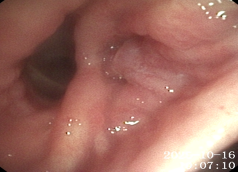

支气管镜:

隆突

左肺下叶开口

右中间支气管

10-20患者出现发热,支气管镜下:左肺下叶开口大量脓性分泌物伴气道痉挛

该患者为马尔尼菲篮状菌的重度感染,马尔尼菲篮状菌病为少见疾病。马尔尼菲篮状菌病(Talaromycosis,TSM)是由马尔尼菲篮状菌引起的侵袭性真菌病。该菌主要侵犯单核-巨噬细胞网状内皮系统,故而容易在淋巴结、肝、脾、肺、皮肤等发生病变。流行病学显示,90%以上病例出现在免疫力受损患者,尤其是艾滋病患者的免疫功能进一步下降,加剧了马尔尼菲篮状菌播散。TSM的影像学表现多种多样,包括大片实变、结节、磨玻璃改变、粟粒样病变、肺门或纵隔淋巴结肿大、胸腔积液、空洞、坏死,以及细菌性肺脓肿,内壁光滑,甚至有气液平面。气管镜下为气道内壁光滑的凸起结节,伪膜、溃疡等少见。